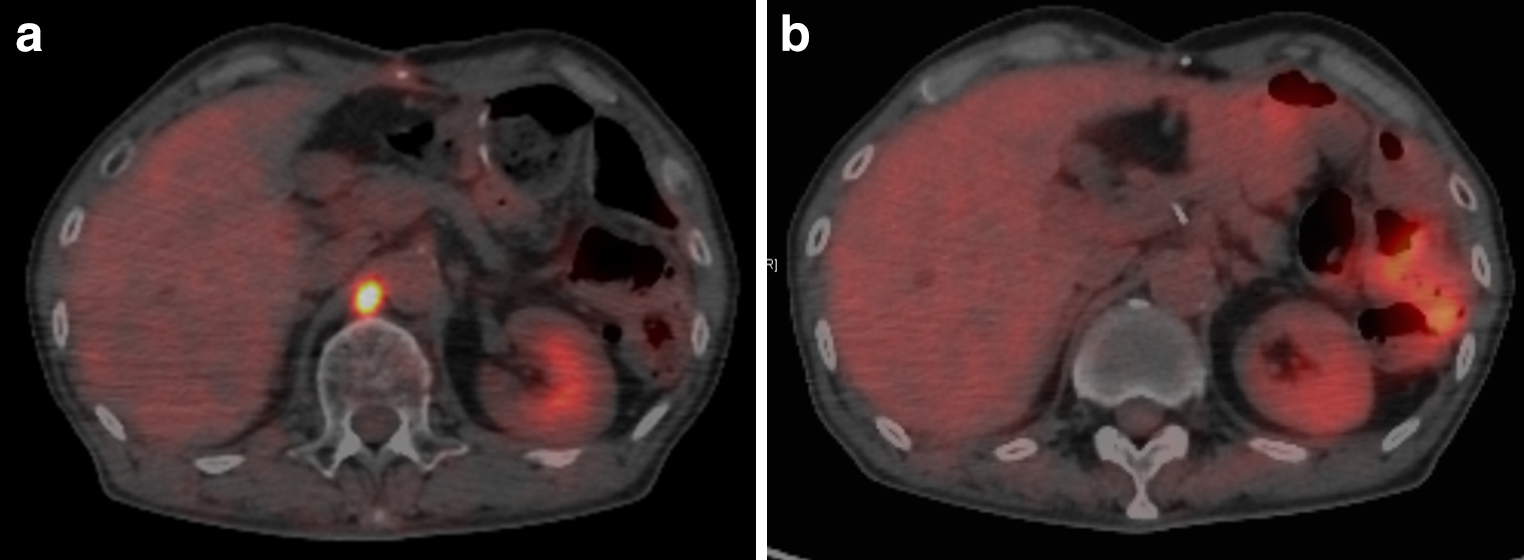

PET-CT所見(術後2か月):大動脈周囲リンパ節腫大を複数認め,同部位に異常集積(SUV=13.6)を認めた(Fig. 5a).

PET-CT revealed swollen para-aortic lymph node and abnormal intake (SUV=13.6) (a). After R-CHOP, abnormal intake in para-aortic lymph node disappeared (b).

治療経過③:血液検査においてはCEA 6.7 ng/ml,CA19-9 21 U/mlと腫瘍マーカーの低下を認めた一方,可溶性IL-2レセプターは791 U/mlと高値を認めていたことから病歴と考え併せてDLBCLの節外病変を疑った.進行期の胃DLBCLの標準治療は化学療法であること,胃DLBCLは化学療法によって治癒が望めることから胃DLBCLに対する化学療法(R-CHOP療法)を優先して行うこととした.3コース施行後の効果判定では可溶性IL-2レセプターは480 U/mlと低下しており,PET-CTにおいても大動脈周囲リンパ節腫大への異常集積は消失しcomplete responce(以下,CRと略記)の判定となった(Fig. 5b).化学療法継続の方針とし4コース目を開始し現在も治療継続中である.